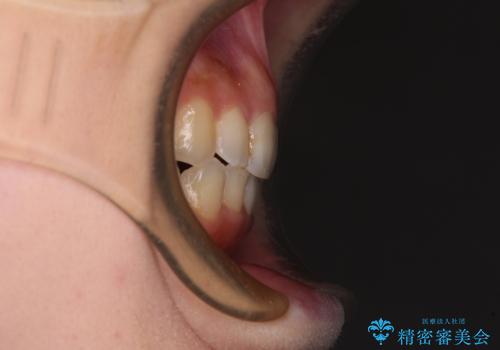

顕著な八重歯をインビザラインで治せるところまで改善

- 顕著な八重歯など、上下前歯のデコボコとスペースを気にして来院された患者様です。

八重歯改善には第一小臼歯の抜歯が必要であり、移動量が多いことから補助装置により八重歯を引き込むこととしました。

補助装置だけでなく、部分的にワイヤー矯正も使用しましたが、上下のスペースは改善しきれず、側切歯(前から2番目の歯)や顕著な八重歯は、インビザラインで治療するには限界があることがよく分かりました。

より良い仕上がりを希望される場合には、ワイヤー装置による矯正治療がお勧めとなります。